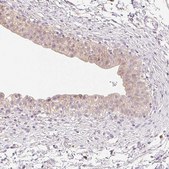

HPA055967

Anti-MBOAT7 antibody produced in rabbit

IF, IHC

immunofluorescence: 0.25-2 μg/mL, immunohistochemistry: 1:200-1:500

All Prestige Antibodies Powered by Atlas Antibodies are developed and validated by the Human Protein Atlas (HPA) project and as a result, are supported by the most extensive characterization in the industry.

The Human Protein Atlas project can be subdivided into three efforts: Human Tissue Atlas, Cancer Atlas, and Human Cell Atlas. The antibodies that have been generated in support of the Tissue and Cancer Atlas projects have been tested by immunohistochemistry against hundreds of normal and disease tissues and through the recent efforts of the Human Cell Atlas project, many have been characterized by immunofluorescence to map the human proteome not only at the tissue level but now at the subcellular level. These images and the collection of this vast data set can be viewed on the Human Protein Atlas (HPA) site by clicking on the Image Gallery link. We also provide Prestige Antibodies® protocols and other useful information.

• IHC tissue array of 44 normal human tissues and 20 of the most common cancer type tissues.